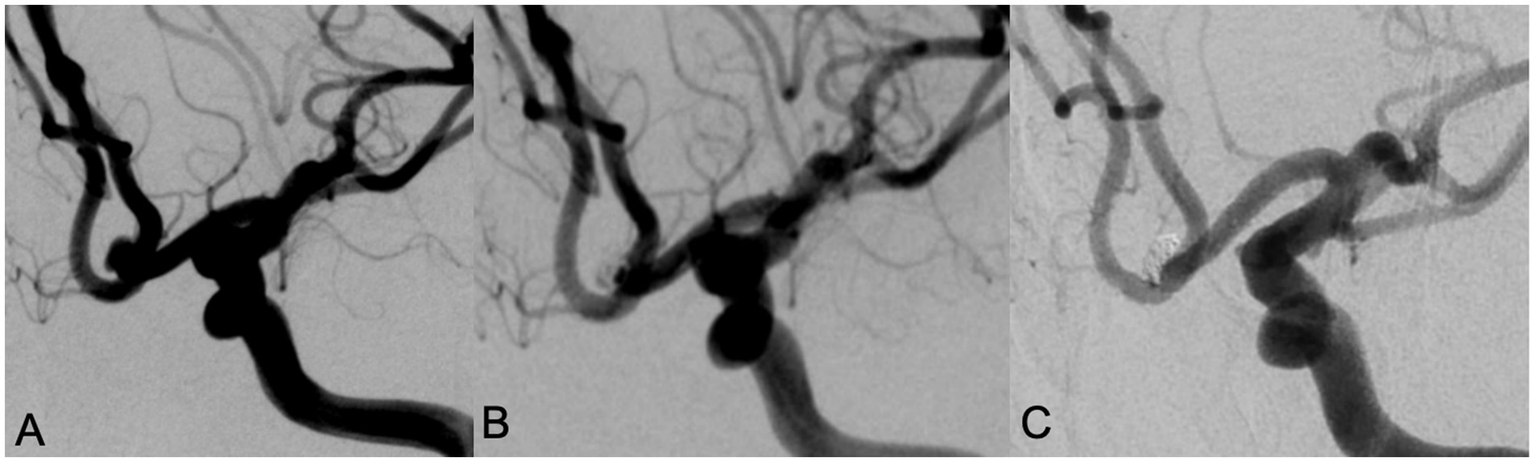

All patients successfully completed SAC for WNIA, and the technical success rate was 100%. Immediate postembolization angiography showed that in the Neuroform Atlas group, 22 aneurysms (81.5%, 22/27) achieved MRRC Class I, 5 aneurysms (18.5%, 5/27) achieved Class II, and 0 aneurysms (0%) achieved Class III. In the LVIS group, 25 aneurysms (73.5%, 25/34) achieved MRRC Class I, 9 aneurysms (26.5%, 9/34) achieved Class II, and 0 aneurysms (0%) achieved Class III. There was no significant difference in the initial obliteration class between the two groups (p = 0.549) (Table 2). Representative cases of the Atlas group and LVIS group were shown in Figures 1, 2, respectively.

Figure 1. A 78 year old female with intermittent headache and left lower limb weakness for 9 days was admitted, DSA examination showed an anterior communicating artery aneurysm with a wide neck (A). Neuroform Atlas stent assisted coiling embolization was performed. Immediate angiography after embolization showed the aneurysm was almost occluded with MRRC grade 2 (B). Angiography performed in 12 months’ follow-up showed that the aneurysm was occluded well with MRRC grade 1 (C).